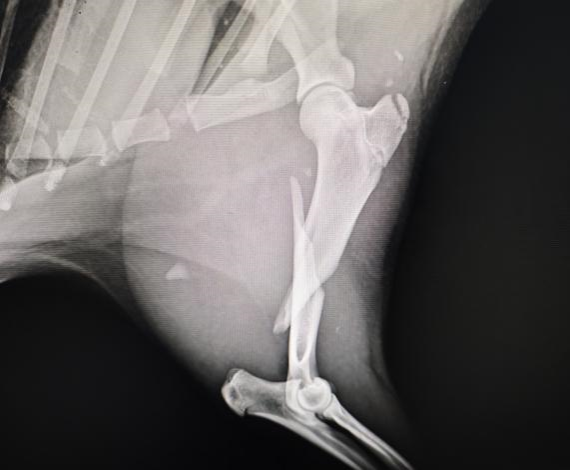

手术前左前肢侧位X光

水豚左前肢跛行

拍摄水豚左前肢X光

水豚,一种原本生活在南美洲亚马逊河流域的珍稀哺乳动物,因其独特的生理结构和萌宠的外貌而备受关注。本次手术的主角是一只因肱骨骨折而生命垂危的水豚。经过专家团队的精心评估和准备,手术于本周初顺利进行。